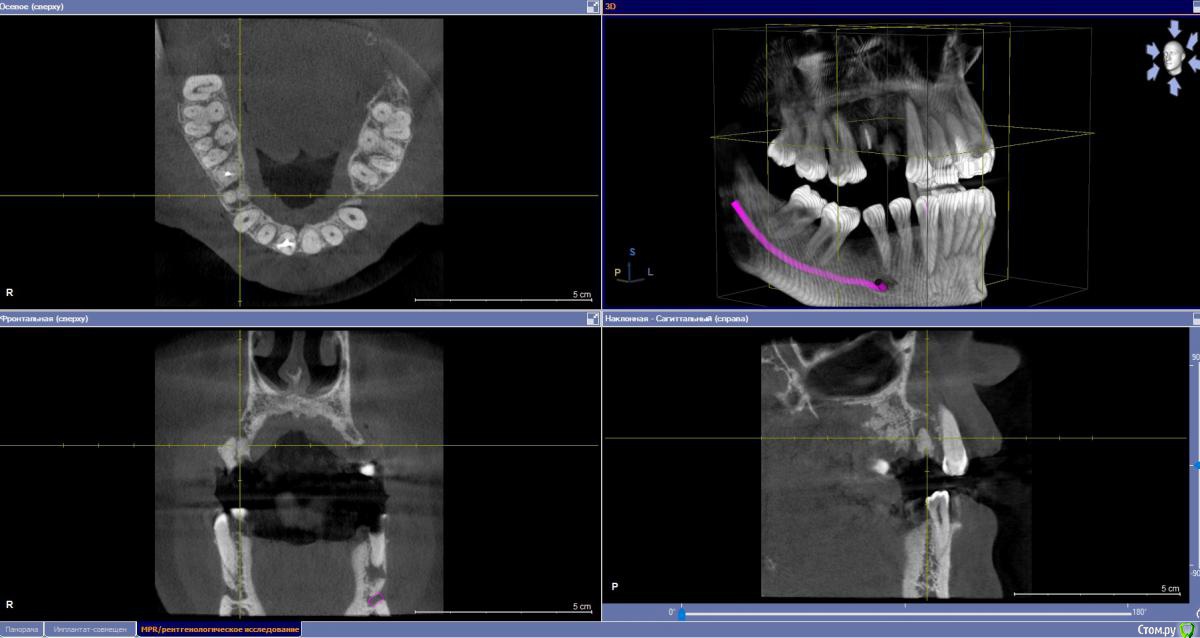

stomalolog Опубликовано 30 ноября, 2018 Поделиться Опубликовано 30 ноября, 2018 Добрый день. Пациенту назначили удаление корней 14,15. Вокруг 14 очаг резорбции, отсутствует вестибулярная стенка, на уровне шеек чуток кости.Собственно вопрос - что после удаления лучше сделать, для образования кости, сохранения десны ? Планируется мостовидный, но в любом случае уйдет десна, если ничего не сделать, не хочется получить яму. И пациент может созреть для имплантации.Какие варианты? A-prf и сверху сразу временные для формирования овоидов и поддержки, или графт-мембрана? Что лучше и может какие еще варианты ?Спасибо. Ссылка на комментарий